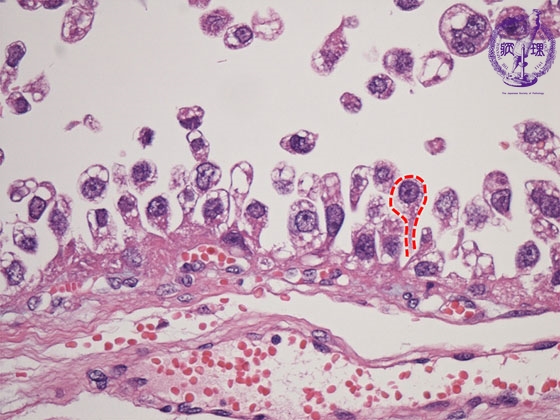

ミクロ像(HE強拡大):淡明な胞体を有する癌細胞がhobnail状(核が細胞の遊離面近くに突出する状態)に増殖している(赤色点線)。 Hobnailは靴底に使われる頭の大きな釘のことをいう。